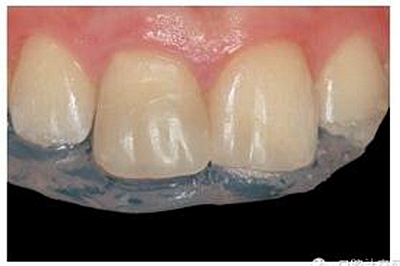

牙本質(zhì)和牙釉質(zhì)經(jīng)過全酸蝕(酸蝕劑)后,涂布粘接劑(Syntac; Ivoclar Vivadent),準(zhǔn)備樹脂修復(fù)。利用已完成的硅膠導(dǎo)板輔助修復(fù)體的腭側(cè)成型(圖13)。牙本質(zhì)核采用不同顏色、不透光的牙本質(zhì)樹脂分層連續(xù)堆積

切端則采用透明樹脂,最后使用釉質(zhì)樹脂(Amaris, VOCO, Cuxhaven, Germany)。21的樹脂修復(fù)采用類似的方式。修復(fù)初步成型,拋光,恢復(fù)干燥牙釉質(zhì)的顏色。攝片顯示樁在根管內(nèi)位置合適(圖15)。最后一次復(fù)診精修、拋光充填體,完成治療。